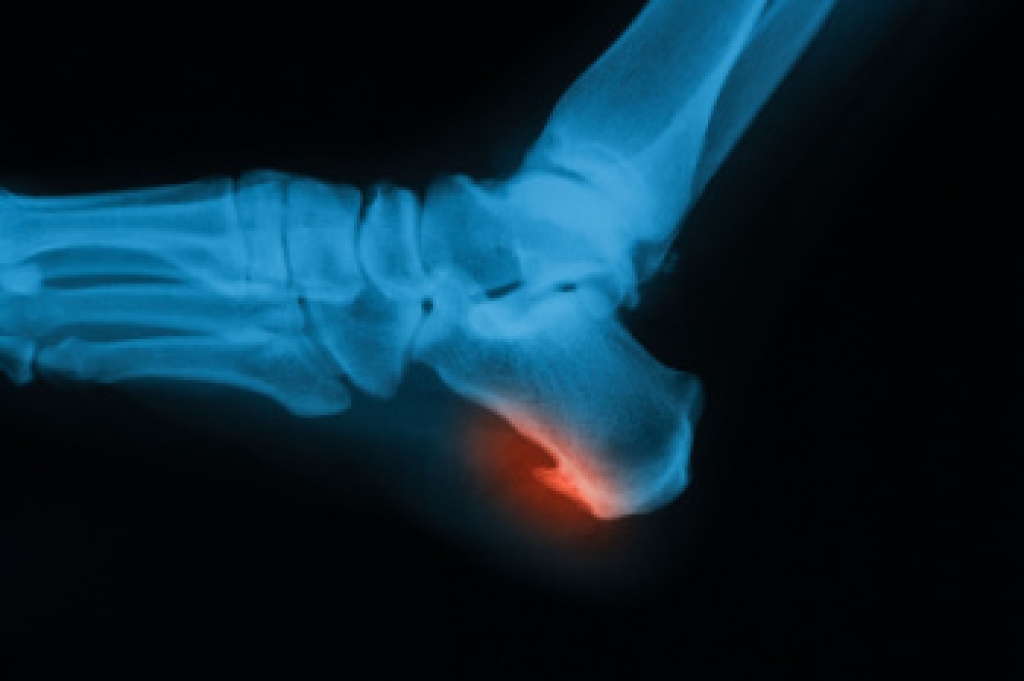

A heel spur is a bony growth that forms on the heel bone, often linked to physical stress, inflammation, or plantar fasciitis. Heel spurs can be classified into four types, including absent, indicating no visible spur. Horizontal spurs grow straight across the heel, vertical spurs point upward, while hooked spurs curve toward surrounding tissues, often causing more discomfort. Symptoms include heel pain, tenderness, and swelling, especially during walking or standing. Causes include repetitive strain, poor footwear, obesity, and high impact activities. A podiatrist can diagnose the type of heel spur, provide targeted treatments, and recommend supportive footwear or orthotics. If you have heel pain, it is suggested that you consult a podiatrist who can provide an accurate diagnosis and treatment.

Heel spurs are formed by calcium deposits on the back of the foot where the heel is. This can also be caused by small fragments of bone breaking off one section of the foot, attaching onto the back of the foot. Heel spurs can also be bone growth on the back of the foot and may grow in the direction of the arch of the foot.

Older individuals usually suffer from heel spurs and pain sometimes intensifies with age. One of the main condition's spurs are related to is plantar fasciitis.

Pain

The pain associated with spurs is often because of weight placed on the feet. When someone is walking, their entire weight is concentrated on the feet. Bone spurs then have the tendency to affect other bones and tissues around the foot. As the pain continues, the feet will become tender and sensitive over time.